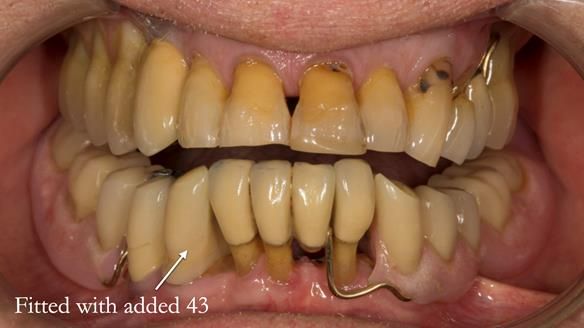

In 2022, tooth 43 fractured.

An artificial tooth was added to the RPD

by welding a cobalt–chrome tag to the bar

and adding the tooth.

The denture continued to function extremely well.

This case was always about function, not aesthetics.

Ken’s teeth were never going to look perfect.

There were stained composites, old restorations, and obvious wear.

That was accepted from the outset.

The way Rowan lengthened the teeth — particularly in the upper RPD — to match the existing gingival recession on the remaining teeth was superb. The dentures sit naturally within the context of the rest of the mouth.